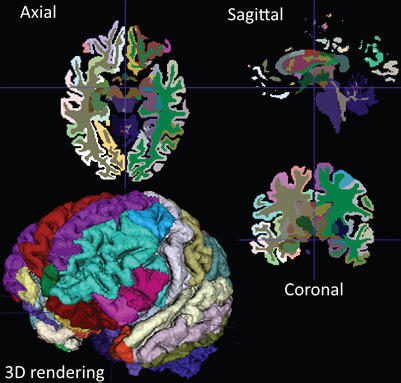

예를 들어, CT 영상 분석에서는 엣지 검출, 분할, 특징 추출, 객체 검출 등의 작업을 수행합니다. 또한, MRI 영상 분석에서는 뇌 성분 분할, 종양 감지, 질환 진단 등에 활용됩니다. 또한, 딥러닝 기술을 이용한 의료 영상 분석은 최근에 많은 연구가 진행되고 있습니다.

3D Slicer: 의료 영상 처리 및 분석을 위한 고품질 오픈소스 플랫폼입니다.

ITK-SNAP: 의료 영상 분할 및 시각화를 위한 오픈소스 소프트웨어입니다.